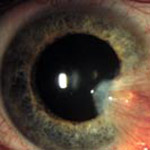

Fuchs' Corneal Dystrophy

An inherited condition that affects the inner layer of the cornea.